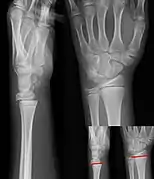

Salter–Harris I fracture of distal radius.

Salter–Harris II fracture of ring finger proximal phalanx.